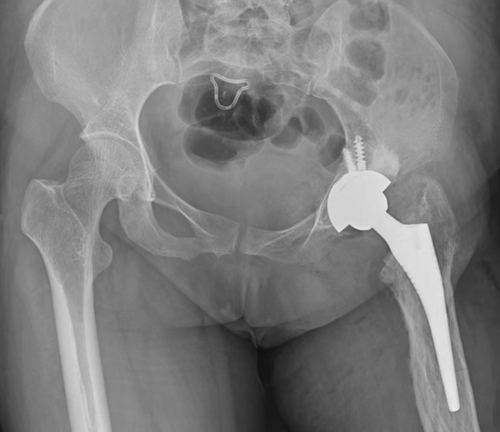

劉建鋒經(jīng)過詳細詢問病史,及完善影像學(xué)檢查,發(fā)現(xiàn)患者由于病史長股骨頭缺失并脫位,整個髖關(guān)節(jié)看起來已經(jīng)融為一體,髖臼發(fā)育差,早已不知“去向”,且髖關(guān)節(jié)周圍骨質(zhì)異常,髓腔骨化消失。經(jīng)測量雙下肢差距達到6cm,患處皮膚有多處骨髓炎竇道瘢痕,病情十分棘手。

經(jīng)手術(shù)團隊多次病情討論、評估,為趙女士“量身訂制”了一套髖關(guān)節(jié)置換手術(shù)方案。術(shù)中的確如術(shù)前預(yù)想的一樣,困難重重,髖關(guān)節(jié)周圍軟組織瘢痕黏連嚴(yán)重,關(guān)節(jié)囊及周圍軟組織攣縮,股骨頭及股骨頸塌陷缺如、髖關(guān)節(jié)增生嚴(yán)重,髖臼基本封閉,無正常形態(tài)……面對眾多挑戰(zhàn),手術(shù)團隊依靠充足的術(shù)前準(zhǔn)備,按照手術(shù)預(yù)案和替代方案,層層突圍,逐一破解,歷經(jīng)兩小時手術(shù)順利完成。

趙女士術(shù)后兩天即能下地行走,雙下肢等長,無任何神經(jīng)癥狀,復(fù)查血管彩超結(jié)果完全正常,復(fù)診拍片位置良好,左髖關(guān)節(jié)功能有了極大改善。術(shù)后患者的恢復(fù)程度及恢復(fù)狀態(tài)都超乎想象,像是獲得了新生,喜悅心情溢于言表。